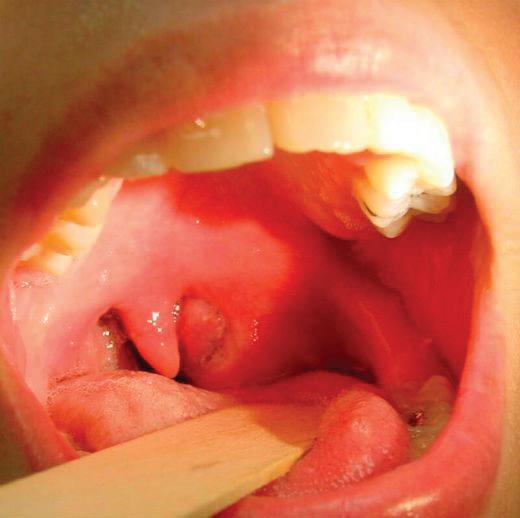

КЛИНИЧНА КАРТИНА

Клиничният преглед цели определяне на сте -

пента на увреждане по отношение на ди -

хателните пътища и гълтателната функция. Мезофарингоскопията дава пълна оценка на устната лигавица, зъбите, слюнчените канали, езика, задна фарингеална стена, небни

дъги, тонзили, форма на твърдо небце, захапка. Понякога фиброоптичната назофарингоскопия може да е полезна в определени случаи, особено при тежък тризъм. Чувството

на сухота в гърлото, дращене и парене, ирадиираща болка към ушите, мъчителен усилен кашличен рефлекс, в началото зачервяване и възпалително оточно разрехавяване на лигавицата, която има сух вид, в последствие се появява слузно-до гнойна ексудация и темпе

ратура 39 0 C са основните клинични симпто

ми, които трябва да следим.